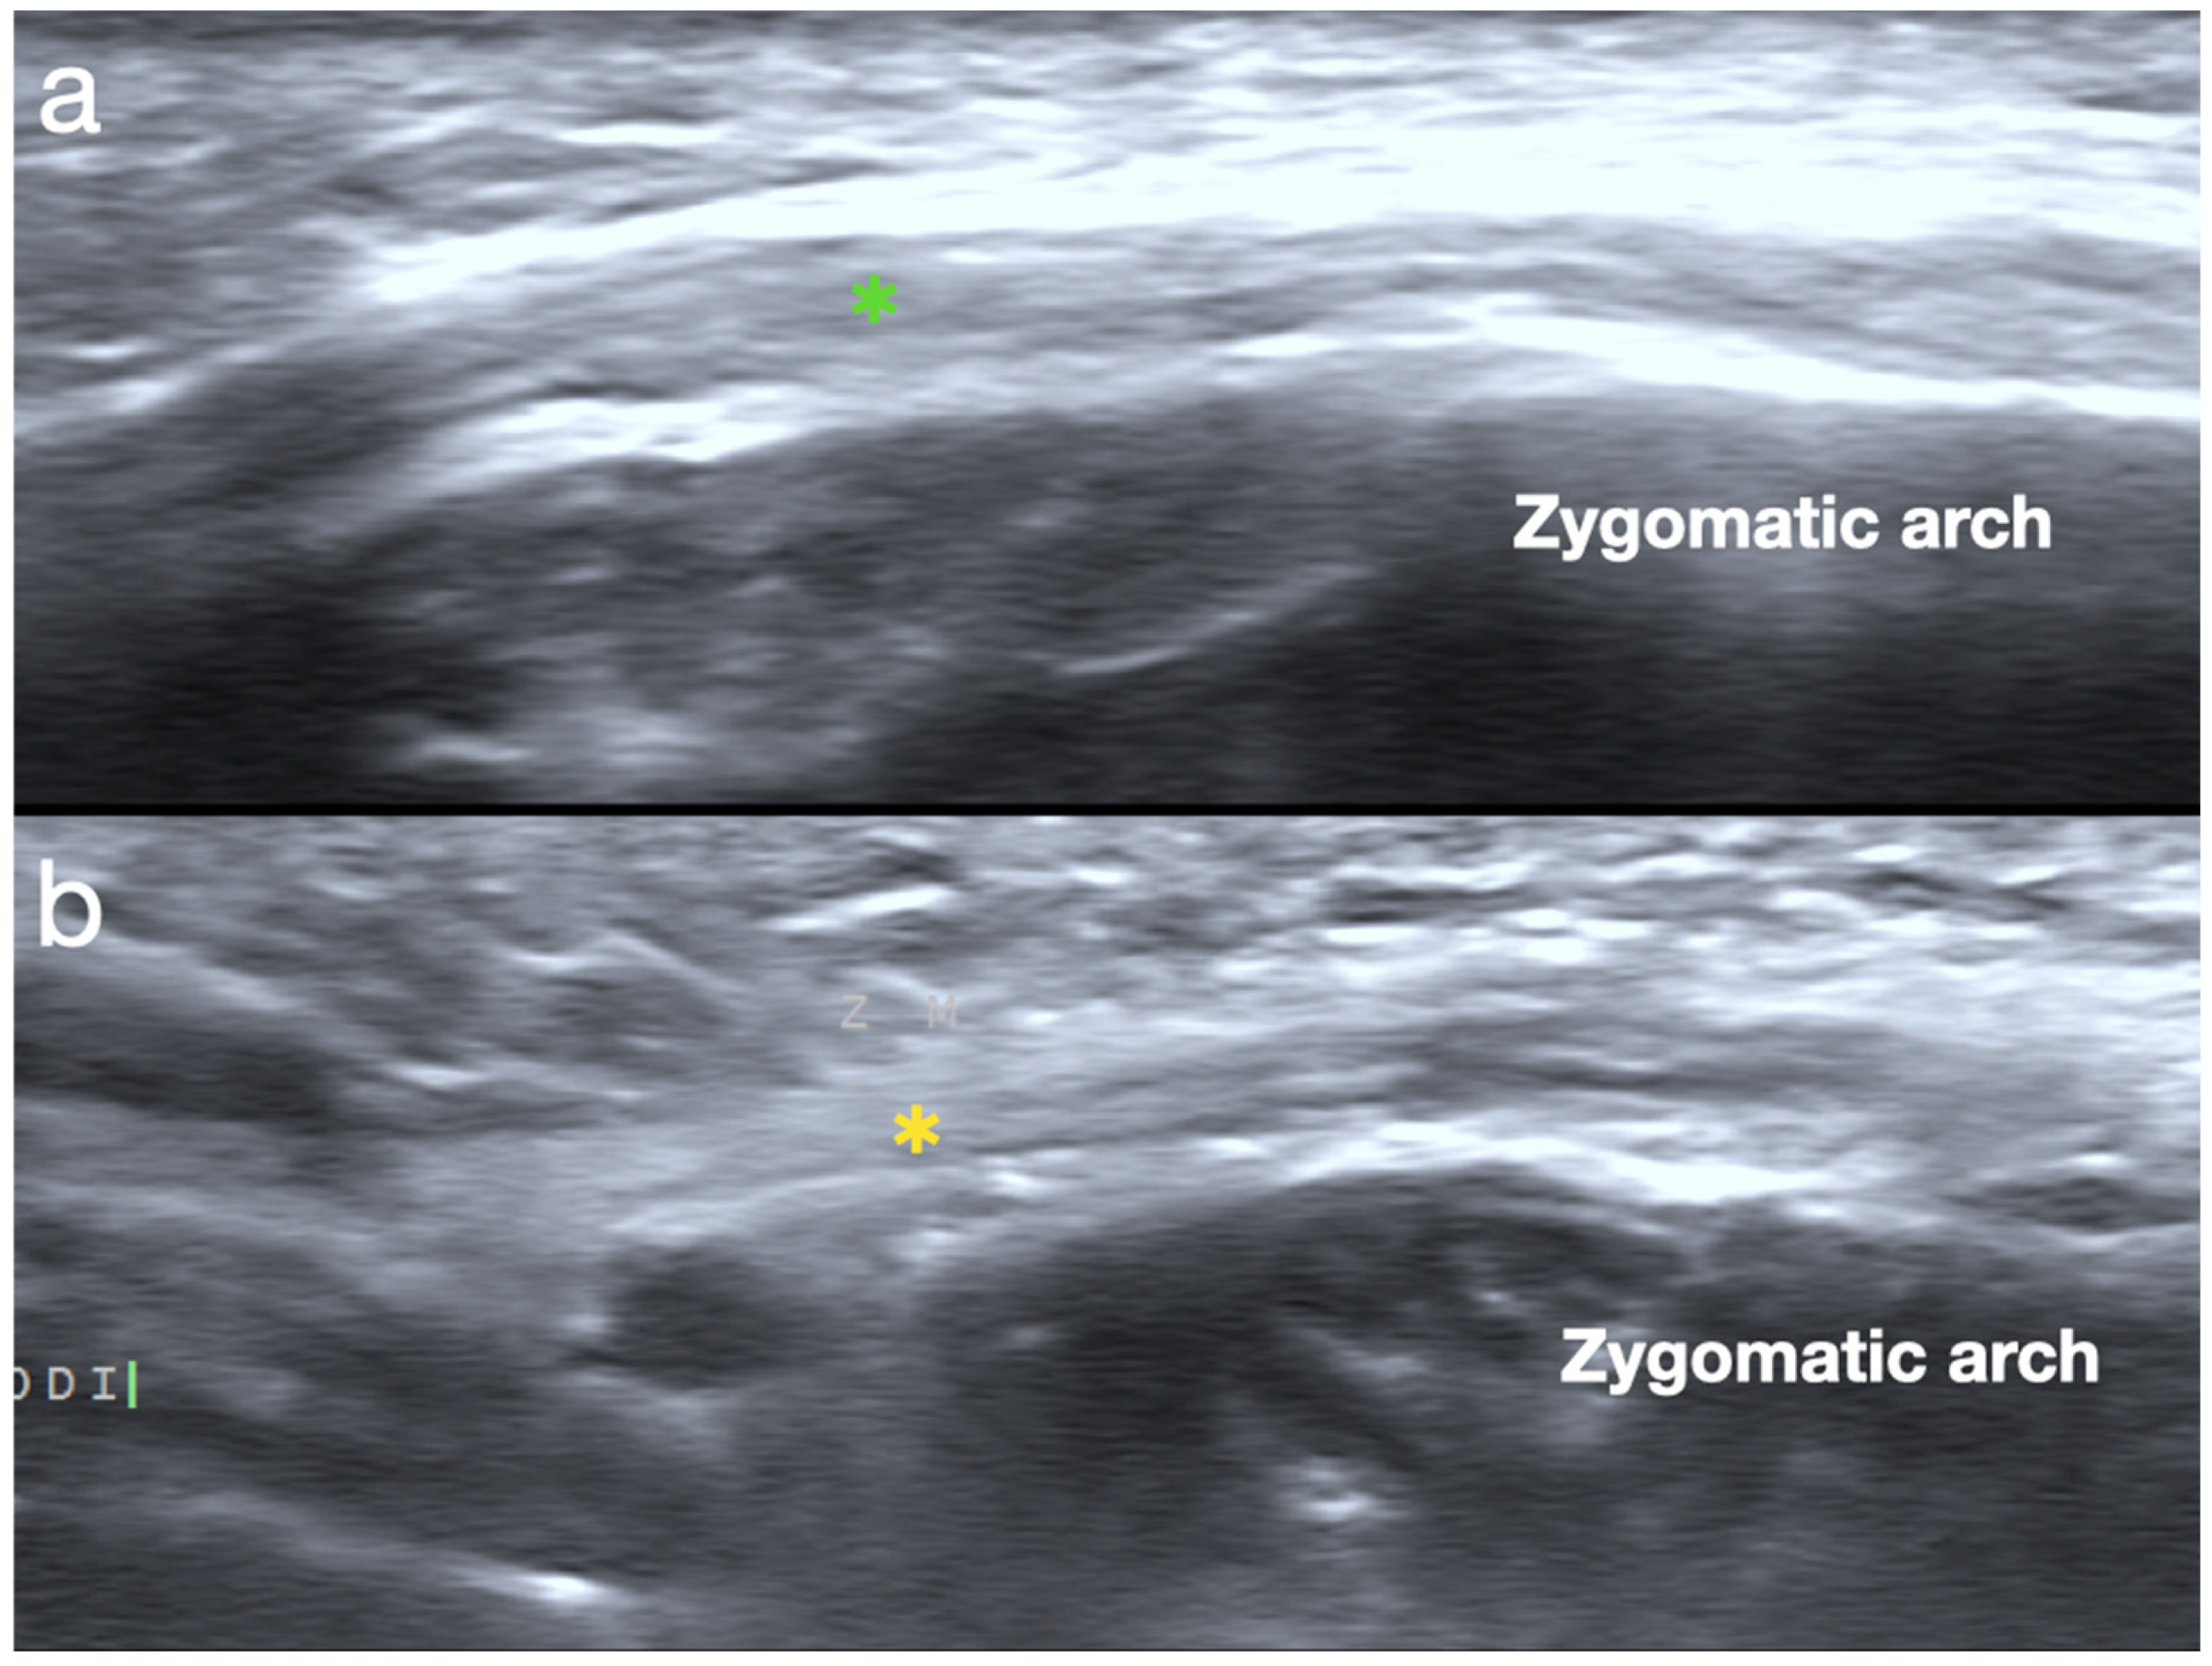

2.1. Sonoanatomy of Peri-Oral Musculature and Fascia System Concerning Embouchure

2.2. Scanning Protocol for the Embouchure in Wind Players